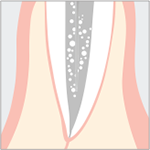

Wurzelkanalreinigung

Entfernung abgebrochener Feilenstücke

Der Vorteil der Ultraschallanwendung für restaurative Eingriffe liegt in der Eigenschaft, dass nur das weichere kariöse Material abgetragen wird, während gesundes Dentin erhalten wird. Zervikal kann der Abtrag kariösen Materials mit minimaler Blutung erfolgen, was eine schnellere Heilung zur Folge hat.